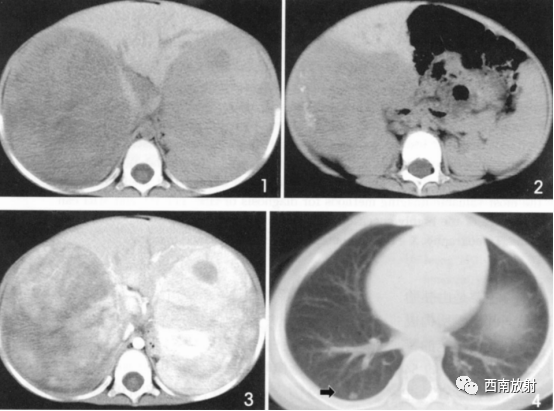

▲病例2:肝母细胞瘤。图1:CT平扫肝左右叶肿块,呈低密度,内部密度不均。图2肝内可见钙化灶。图3增强扫描肝内病灶不均匀明显强化,片状或结节状强化,见假包膜结构,图4可见肝内转移灶。